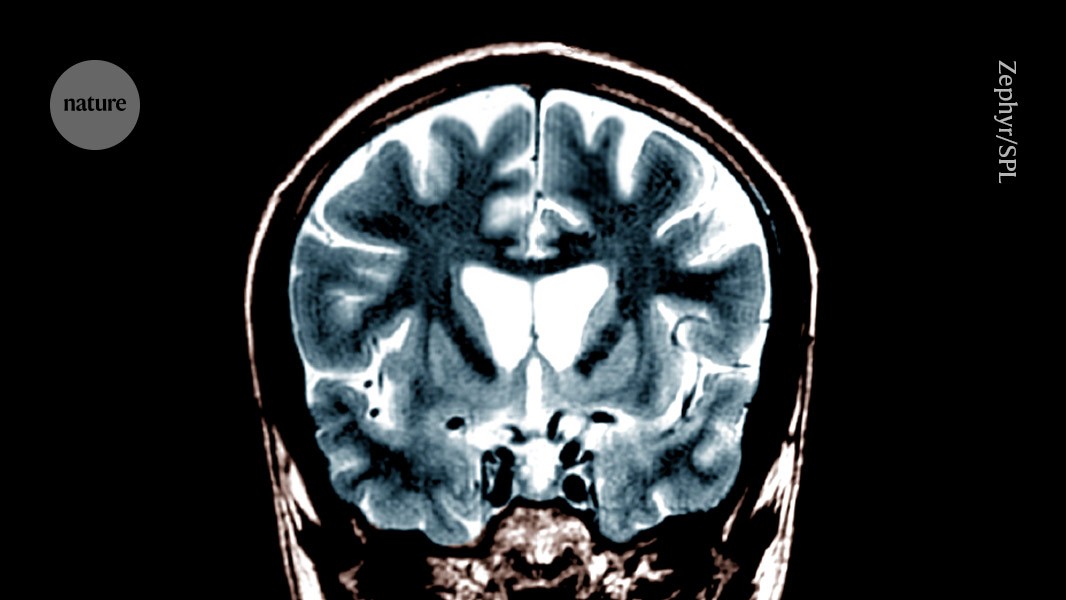

The Nature of Huntington’s Disease

Typically, Huntington’s disease symptoms worsen gradually, usually emerging between ages 35 and 55. What may start as minor coordination issues or forgetfulness can escalate to involuntary movements, mood swings, and significant memory and cognitive decline.

The disorder is driven by repetitive DNA sequences within the huntingtin gene, which leads to the production of a malfunctioning protein that damages brain cells. Currently, there are no treatments targeting the underlying genetic issue, leaving patients to manage only the symptoms.

Administering the therapy involves a substantial surgical procedure where clinicians use magnetic resonance imaging to precisely position a cannula in the skull, slowly infusing the treatment into the striatum, a brain region heavily affected by Huntington’s disease.